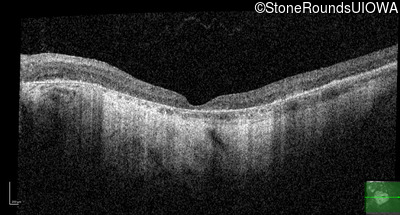

Age at visit: 62 years

This 62 year old man first noted mild distortion in his vision in his 30's, but has always been correctable to 20/20. One year ago an optometrist told him there were pigment abnormalities in his macula.

Diagnosis & molecular findings

Disease Gene Allele 1 variant(s) Allele 2 variant(s) Inheritance mode

Pattern Dystrophy PRPH2 Lys153Glu AAG>GAG   AD